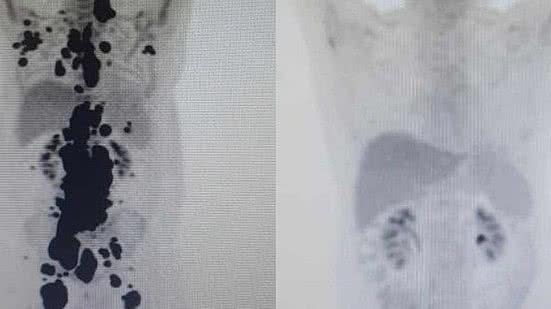

Duas imagens de pet scan, tomografia com uso de contraste, viralizaram nas redes sociais e entre as comunidades médicas ao revelarem o desaparecimento de diversos tumores em um mês de tratamento. Para viabilizar o CAR-T Cell, os pesquisadores brasileiros promovem a reprogramação das próprias células do paciente para atacar e destruir o câncer de forma precisa.